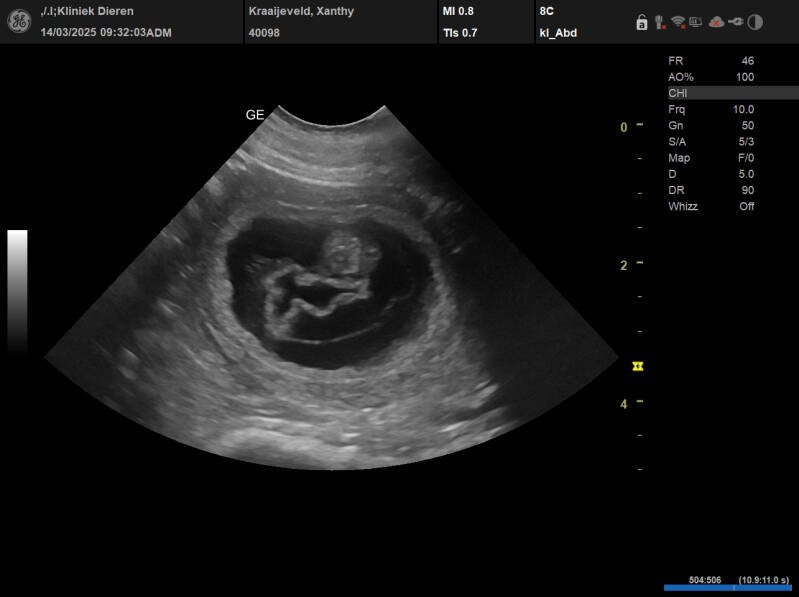

Today is an exciting day. Although I think Xanthy is pregnant, it is always exciting whether it really is.

Richard also came along for the ultrasound. He had never seen an ultrasound like that before. We were called by the vet and Xanthy was allowed to stand on the examination table. She got gel on her belly and the vet quickly went over the belly. I immediately saw that Xanthy was pregnant and so did the vet.

We then looked calmly and the vet explained it to Richard. He did see a number of puppies.

We are so happy. There will be those nice little cuddles again.